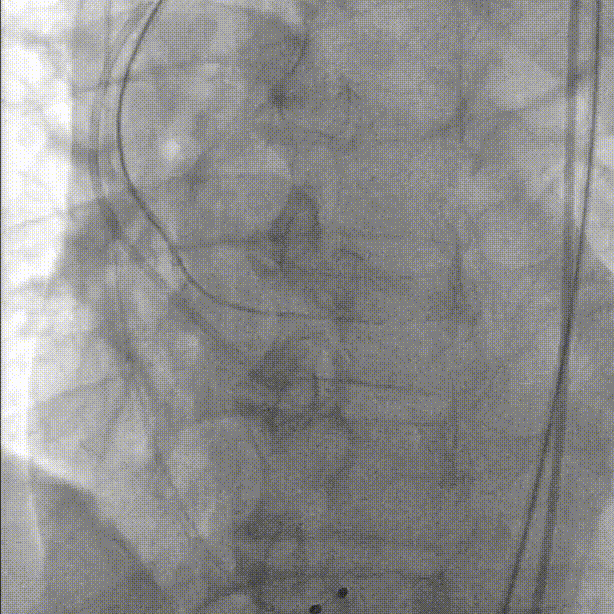

直头导丝跨瓣:

导管测压,压力阶差60mmHg: